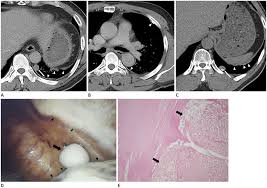

Asbestos Related Calcified Pleural Plaques Can Appear In Various Shapes Download Scientific Diagram

Asbestos Related Calcified Pleural Plaques Can Appear In Various Shapes Download Scientific Diagram from www.researchgate.net

Experience in the field of asbestos related radiological changes. We concluded that asbestos related pleural plaques can under special. Pleural plaques are observed in most cases of asbestosis (98.5%) but not ipf (p < 0.001). Department of radiology, university of british. Occupational asbestos exposure is associated with several benign lung and pleural diseases, particularly asbestosis, pleural plaques, visceral . Therefore, pulmonary fibrosis associated with pleural . Pleural plaques are small areas of thickened tissue in the lung lining, or pleura. There are innumerable pleural plaques, seen mostly en face. Pleural plaques were defined as areas of pleural thickening. Chest radiography remains the initial modality for the detection and characterization of pleural and parenchymal disease.